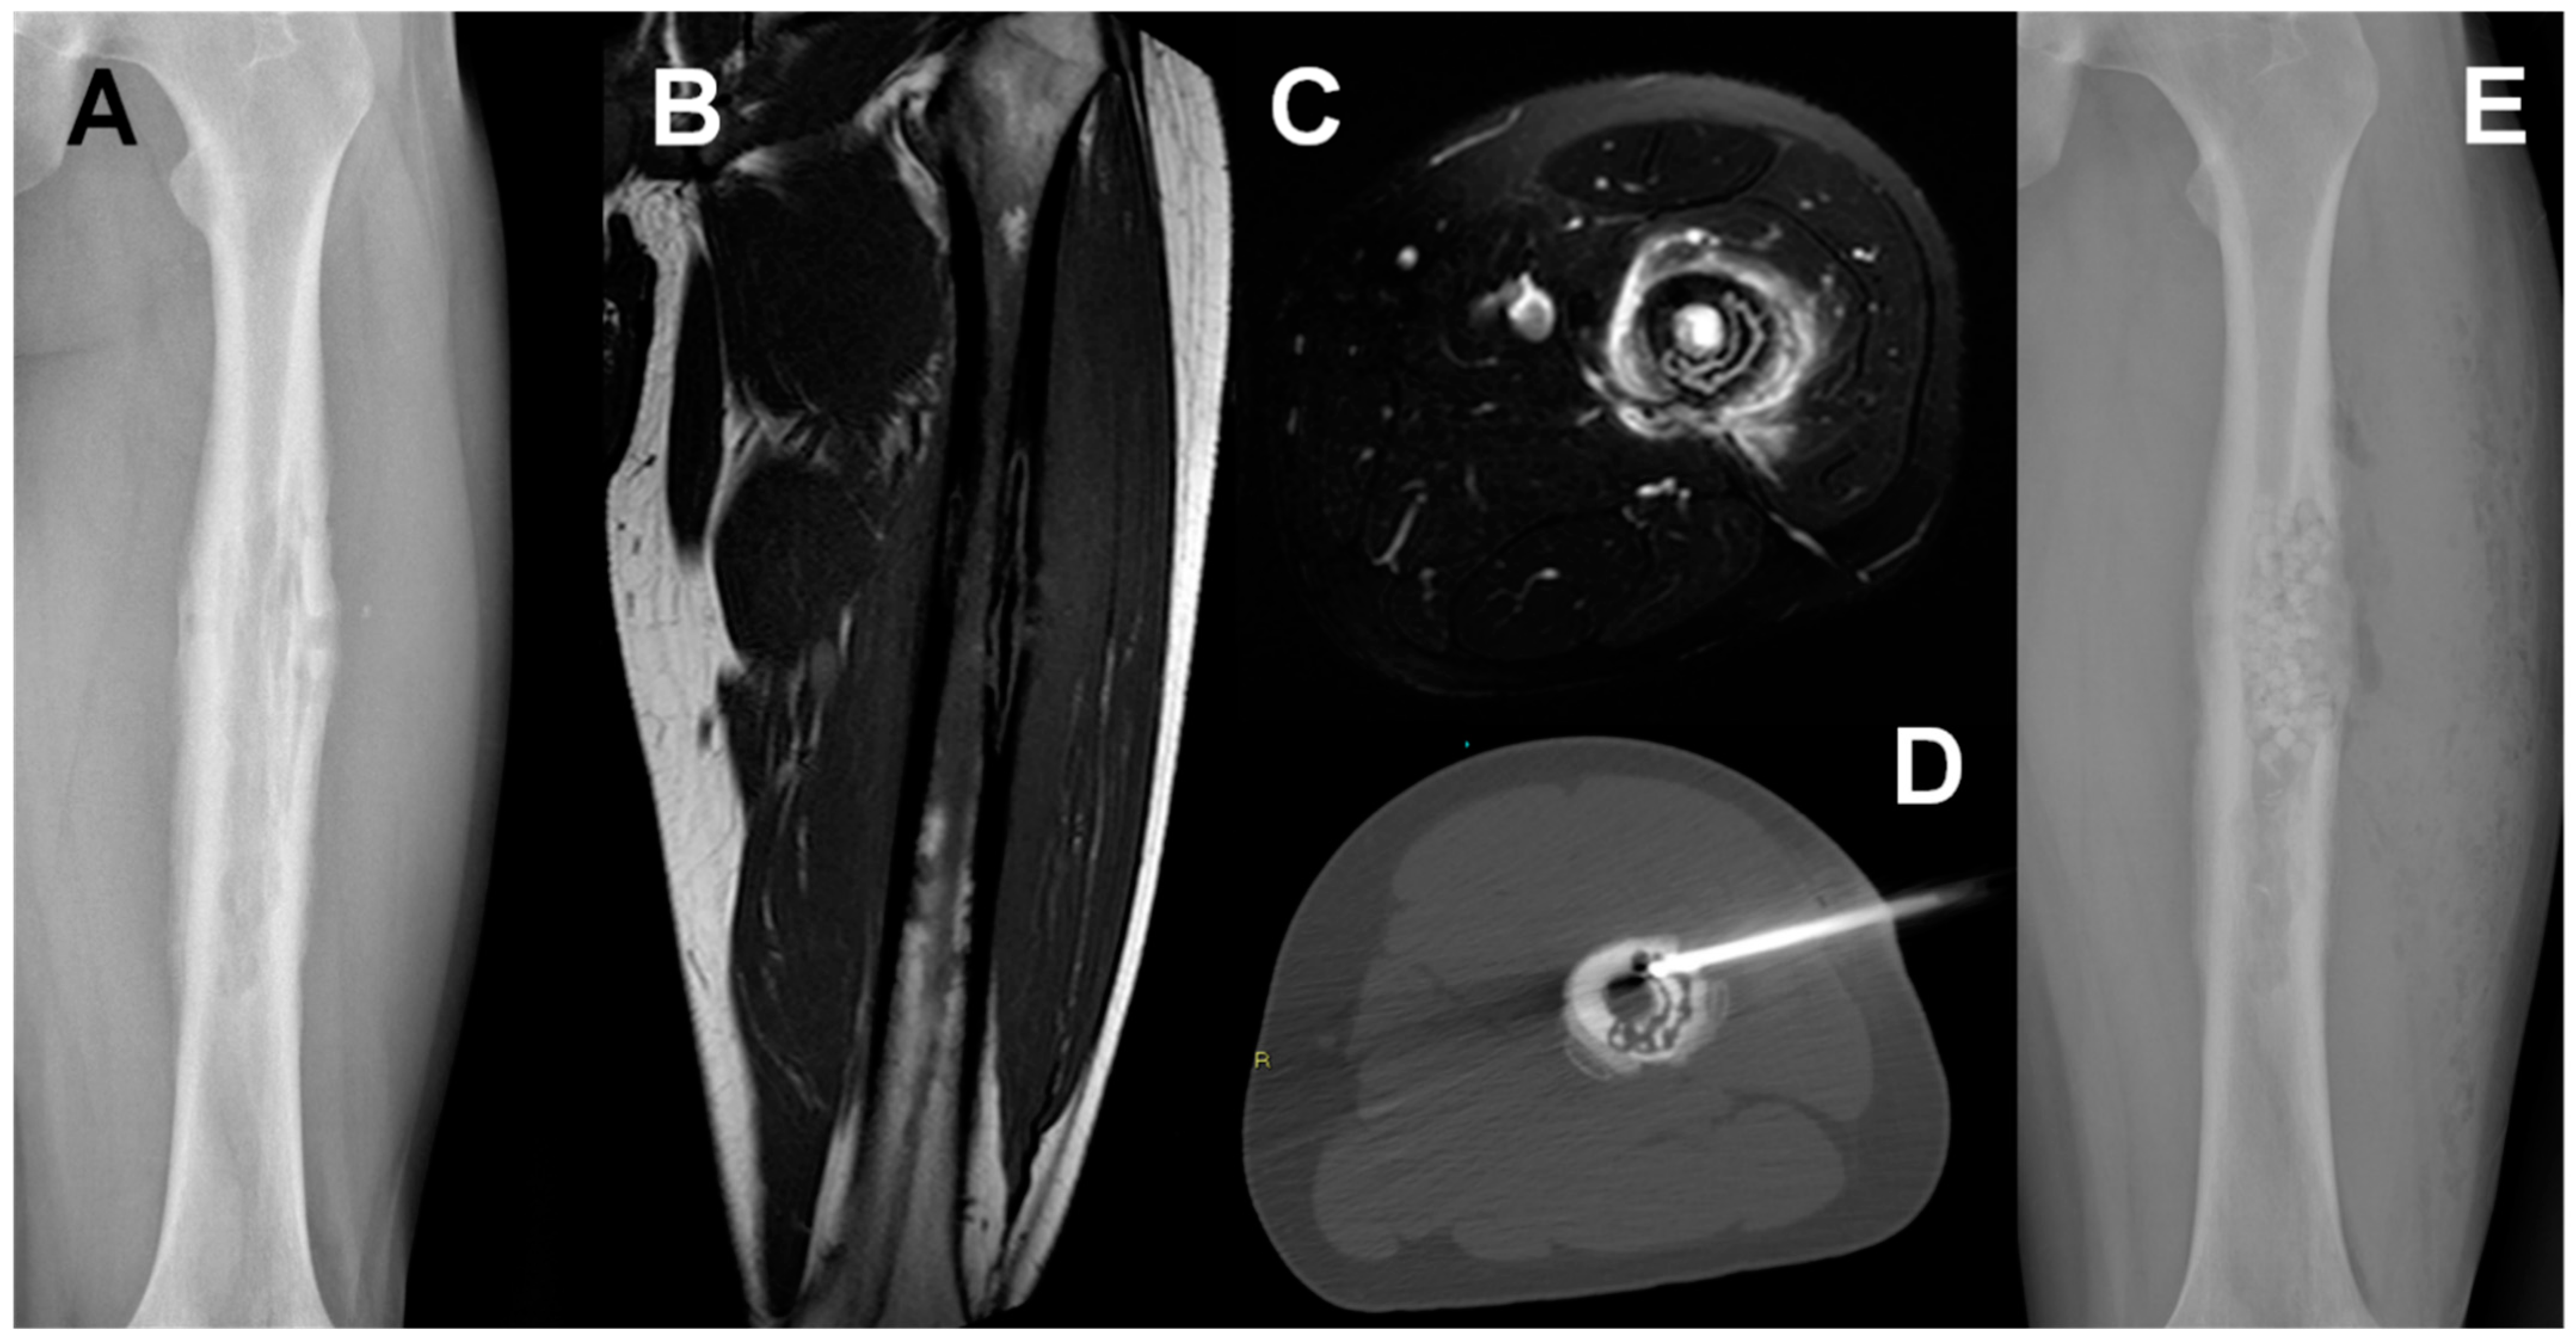

4. Chronic Osteomyelitis